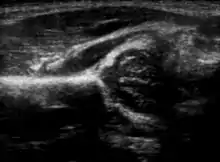

Hip dysplasia can be diagnosed by ultrasound[40] and projectional radiography ("X-ray").[41] Ultrasound imaging is generally preferred at up to 4 months due to limited ossification of the femoral head up until then, and is the most accurate method for imaging of the hip during the first few months after birth. However, in most instances, ultrasound screening should not be performed before 3 to 4 weeks of age because of the normal physiologic laxity.[42][notes 1] When universal with targeted ultrasound screening was compared, the former results in an insignificant reduction in the late diagnosis of hip dysplasia, which is why universal ultrasonographic screening of newborn infants is not recommended by the American Academy of Pediatrics.[11]